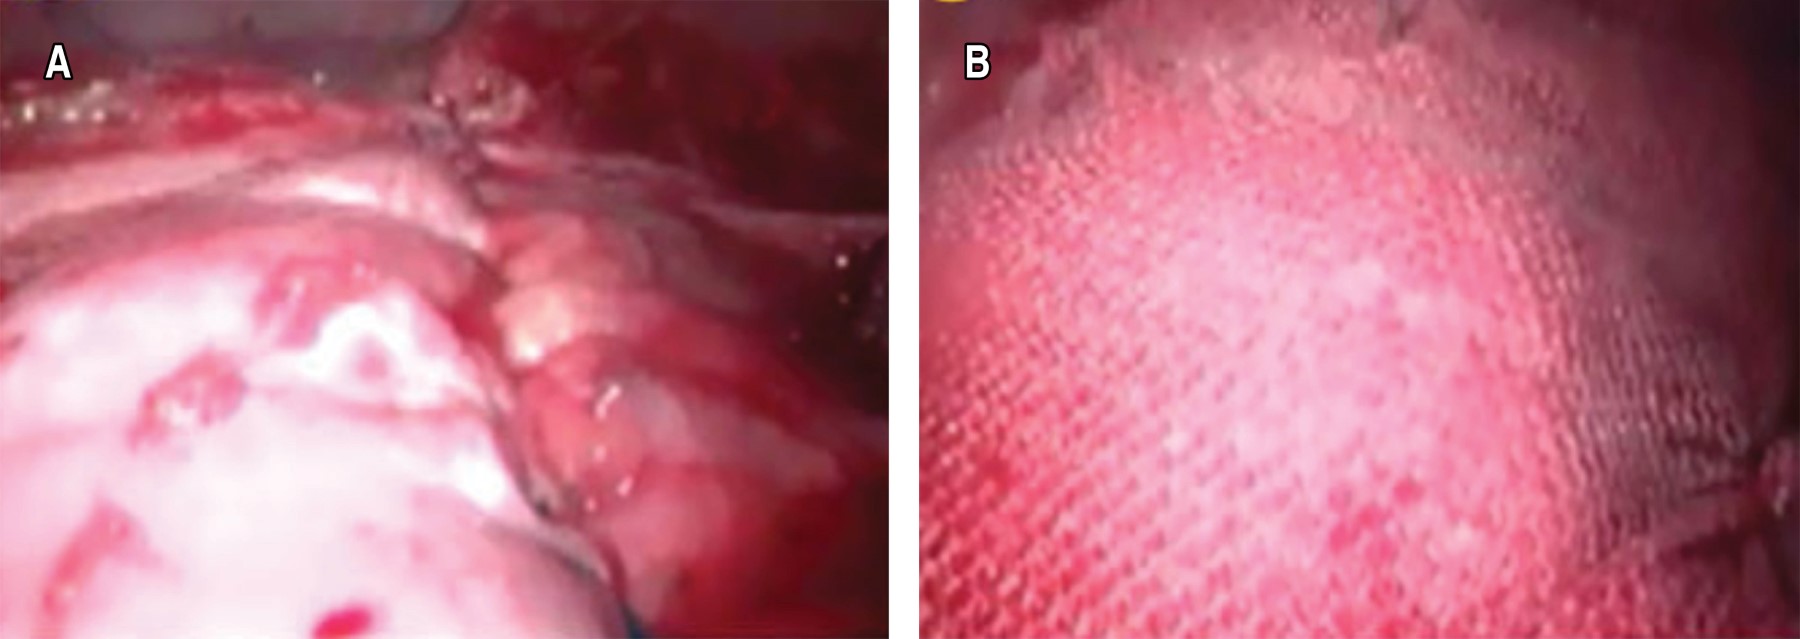

Plastía diafragmática y pleurodesis química por videotoracoscopia: una alternativa como tratamiento quirúrgico en paciente con hidrotórax hepático

Rodríguez-Blanco, José Antonio1; Acevedo-Pérez, Yulieth1; Rodríguez-Blanco, Jonathan1; Remolina-Medina, Carlos1